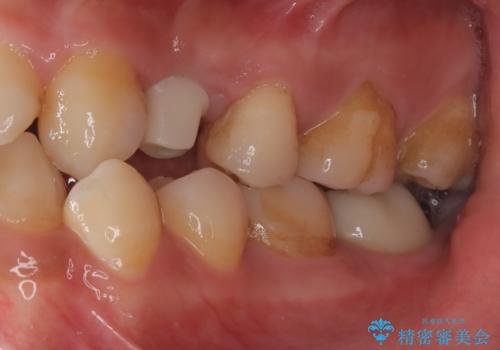

- 440,000円(インプラント体220,000円+カスタムアバットメント110,000円+オールセラミッククラウン110,000円)費用は治療当時の料金となります

長い間虫歯を放置していたため、根っこだけになっている状態でした。このままでは被せ物を被せられないため抜歯を行い治癒を待った後にインプラントを埋入しオールセラミッククラウンで治療を行いました。